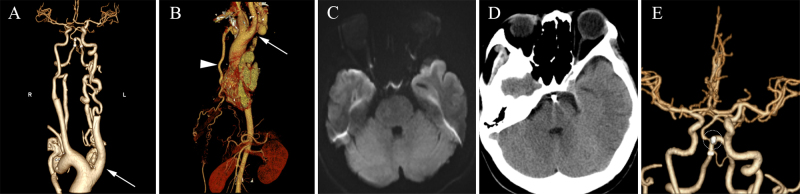

Observations: A 33-year-old female presented with a ruptured VBJ saccular aneurysm (2.0 × 4.1 × 2.9 mm). Emergency right transradial stent-assisted coiling achieved complete occlusion (Raymond-Roy Occlusion Classification class I). Associated anomalies included 1) Celoria-Patton type B IAA, 2) diffuse basilar hypoplasia, and 3) proximal basilar occlusion. Echocardiography confirmed isolated Celoria-Patton type B IAA. Postoperative MRI performed on day 4 revealed no infarction, and CT performed on day 12 confirmed subarachnoid hemorrhage (SAH) resolution. The patient was discharged neurologically intact (modified Rankin Scale score 0). Seven-month CT angiography demonstrated stable coils, an intact stent, and patent vertebral arteries.

Lessons: In adults or adolescents with aneurysmal SAH, IAA typically manifests as an isolated anomaly pathologically linked to prenatal development of robust compensatory collateral circulation supplying the descending aorta. This case demonstrates a synergistic pathogenesis involving two critical hemodynamic factors: proximal basilar artery occlusion combined with type B aortic arch discontinuity, collectively promoting VBJ aneurysm formation. Transradial endovascular intervention proved safe and effective in this anatomically complex scenario. https://thejns.org/doi/10.3171/CASE25421.